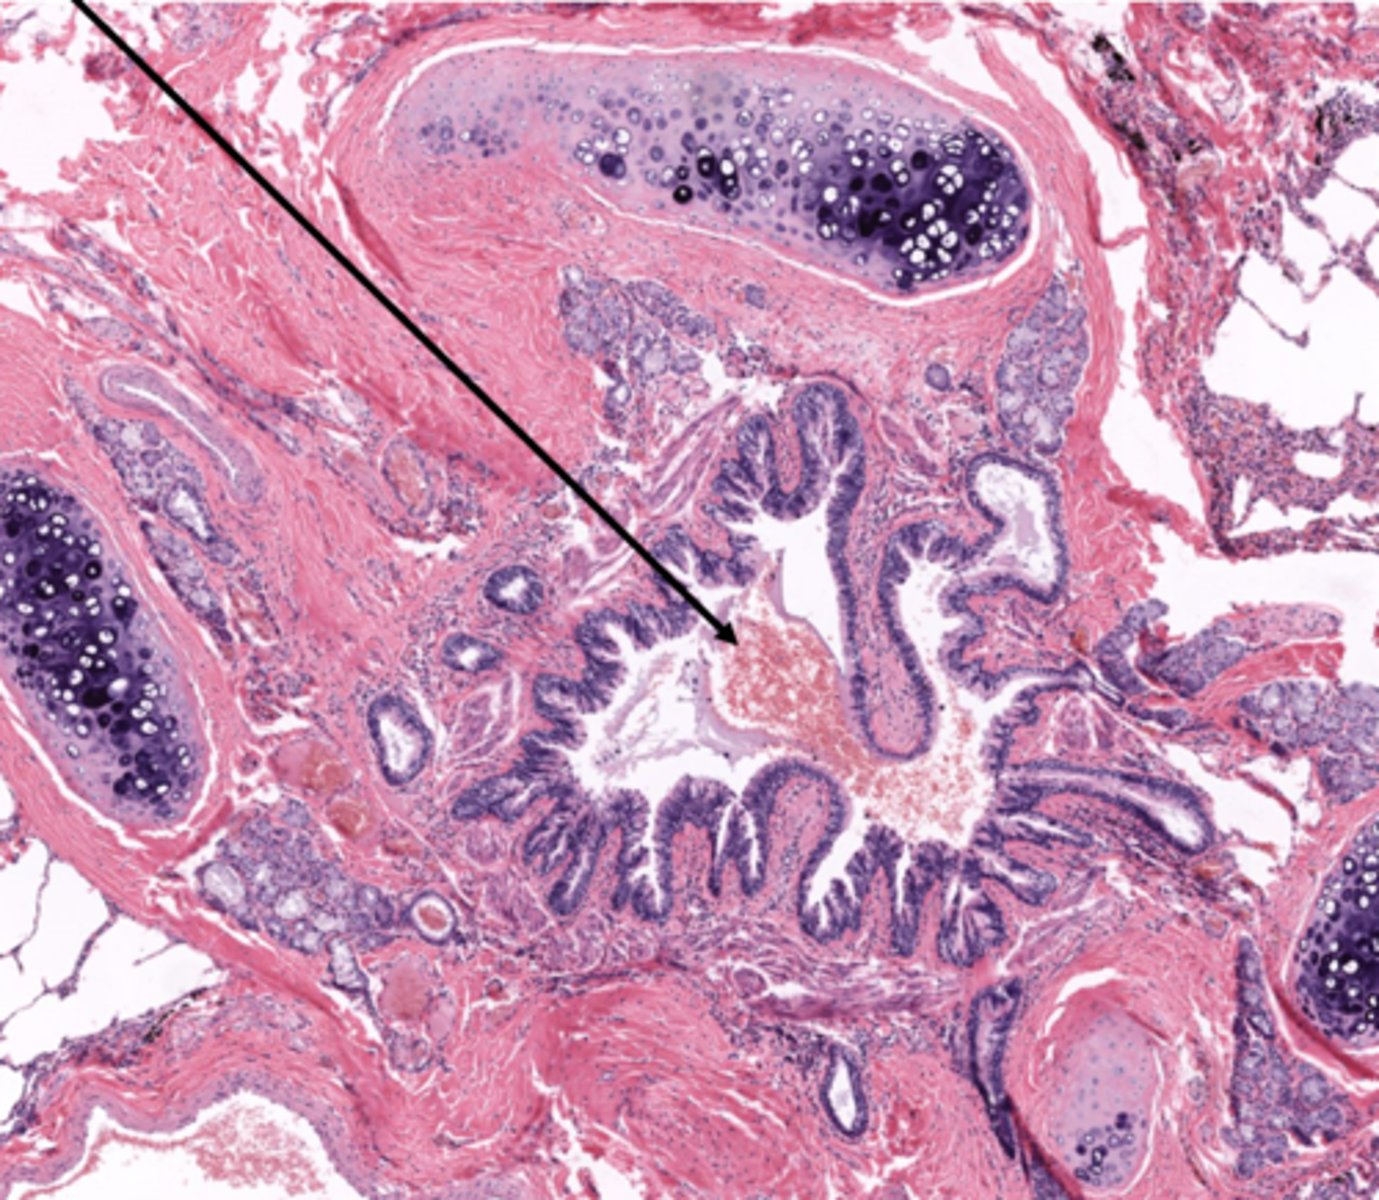

Identify the duct in cross section of the urinary system

ureter

Identify the layer of the ureter

transitional epithelium

lamina propria

Identify the layer of the bladder at 4

smooth muscular wall